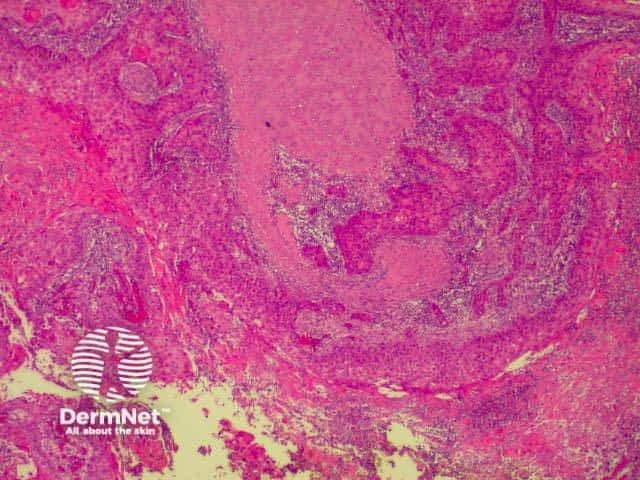

Basal call carcinomas (BCC) have a variety of histological subtypes. Link ta clinical description of basal cell carcinoma.

Various descriptive terms may be used, but there are four main types (more than one pattern may be present in any one tumour).

| Nodular BCC | A well demarcated tumour without significant infiltration in surrounding tissue. |

| Superficial BCC | A poorly demarcated tumour that histologically is composed of small isolated islands of tumour attached to the base of the epidermis. In reality these are probably all connected, but the connections cannot be seen in the two-dimensional section therefore assessment of the margins of these tumours is difficult. |

| Infiltrative BCC | These lesions are composed of small islands of tumour cells which do not form a cohesive mass, but which diffusely infiltrate in the dermis and subcutis. The margins are difficult to define clinically and sometimes histologically. These tumours are therefore often incompletely excised initially. They have a tendency to recur aggressively if not completely removed. They may also show perineural invasion, and if so, the margin of clearance needs to be wider still as there is even more risk of aggressive behaviour. If these tumours are accompanied by stromal fibrosis, they may be referred to as ‘morphoeic’. |

| Micronodular BCC | These lesions are composed of small islands of tumour cells which are diffusely scattered in the dermis rather than circumscribed as are nodular tumours. They are prone to local recurrence if not excised with a satisfactory margin, and they may show perineural invasion, but are not as aggressive as infiltrative tumours. |

The histological features of basal cell carcinoma are typically:

Pathology of BCC Pathology of BCC